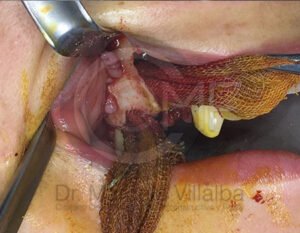

Un absceso es una acumulación de infección que puede causar dolor intenso e inflamación. Cuando el proceso infeccioso no mejora con tratamiento convencional, puede ser necesario realizar un drenaje o manejo quirúrgico.

Es una conexión entre la cavidad oral y el seno maxilar que puede ocurrir tras extracciones o infecciones. Su tratamiento busca cerrar adecuadamente la comunicación para evitar molestias e infecciones sinusales.

El tratamiento depende del origen y gravedad de la infección. Puede incluir medicamentos, drenaje quirúrgico o procedimientos específicos para eliminar el foco infeccioso y evitar complicaciones.

En casos de mayor complicación deberá ser ingresado a cuidados hospitalarios, y programar el procedimiento quirúrgico que corresponda